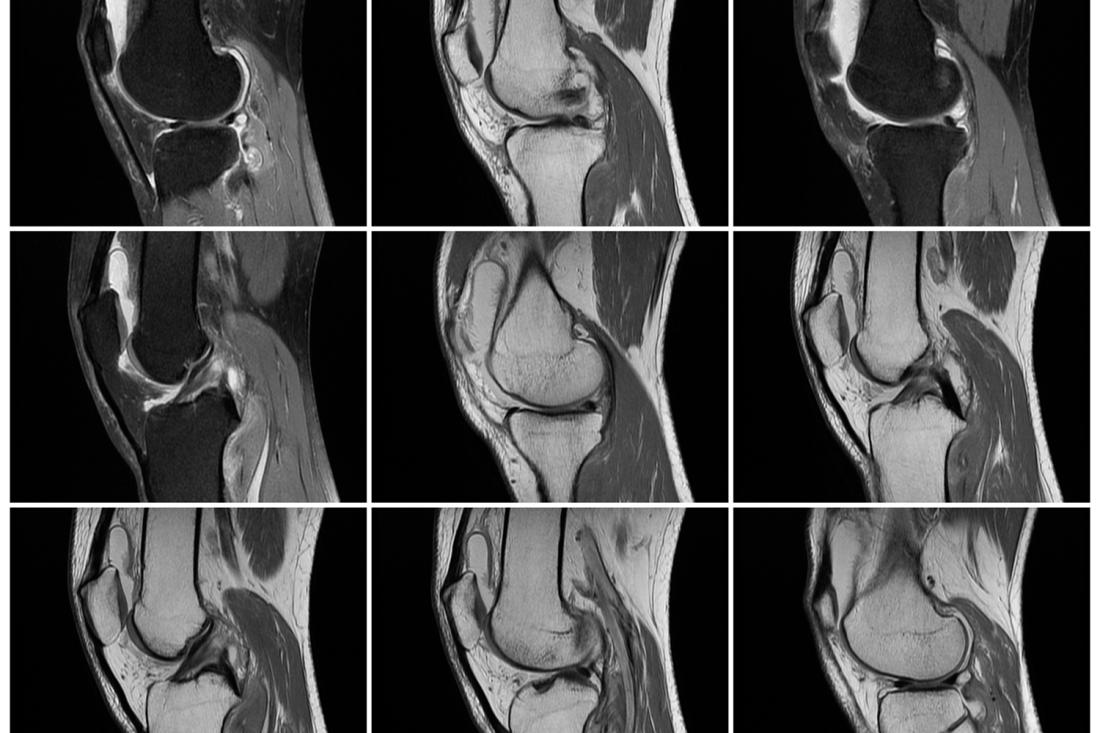

核磁共振检查(MRI)可以显示关节多方位的图像,对组织的分辨率高,可以清楚的显示关节囊、关节腔、关节软骨、韧带、肌腱、滑膜以及周围软组织的信号改变,因此出现关节肿胀、功能障碍症状时,可通过MRI对关节病型银屑病进行诊断。

具体的操作方法:使用MRI仪,采集技术包括T1加权及T2加权成像,反转恢复序列,压脂序列等采集序列。观察踝关节周围软组织有无异常、肌腱有无病变、骨性关节面是否光滑、骨质有无破坏、关节腔有无积液及骨髓有无异常等。

在检查结果中,骨髓水肿、肌腱肿胀及腱鞘周围软组织水肿等,是关节病型银屑病的早期表现,骨质破坏、关节半脱位或骨质增生等,是关节病型银屑病的后期表现,出现骨侵蚀表现为骨皮质连续性中断。